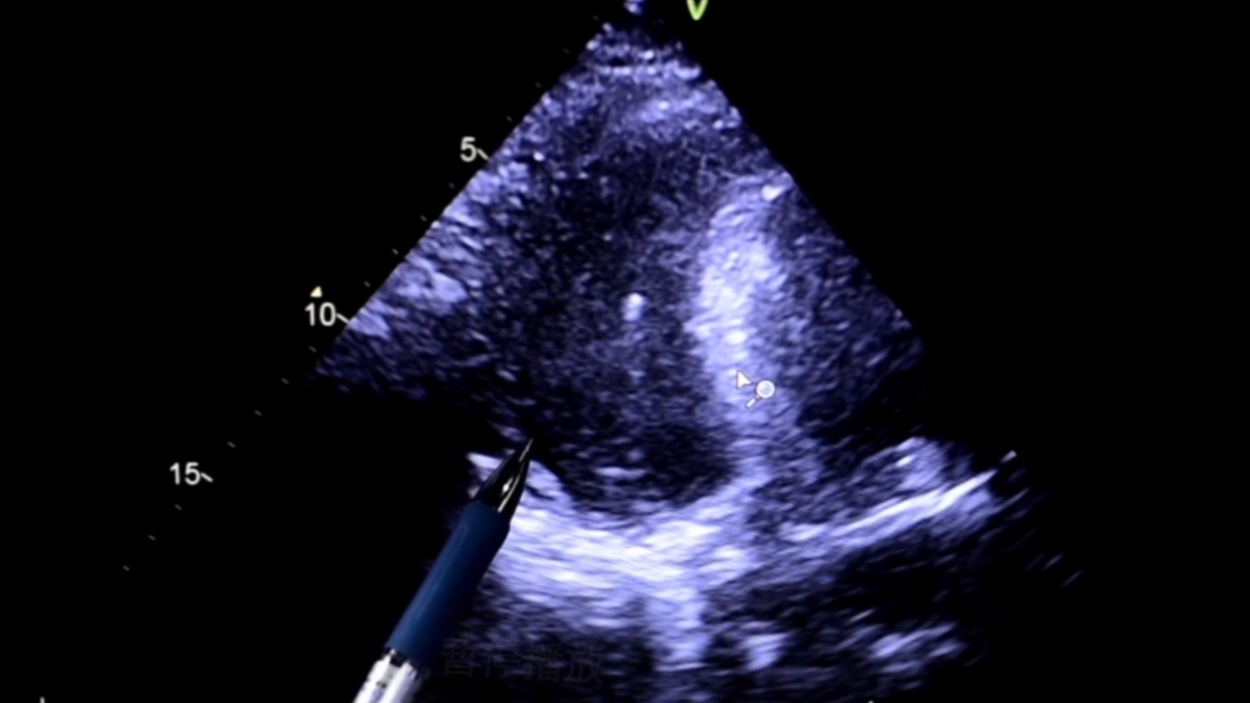

这个图像就是患者当时的心脏。相对颜色比较深的区域,就是大姐的比较局限、位置比较怪异的,心包积液的范围。旁边鼠标所在、比较发亮的区域,是心脏的肌肉,就是心室壁。

沿着超声的指引的方向,一步一步,实时引导,不让针扎到心脏或者其他的一些组织和结构。

这个亮点,就是最后穿到了心包积液里边,针尖所留下的这一个图像,确保了安全、准确、有效的诊疗效果。